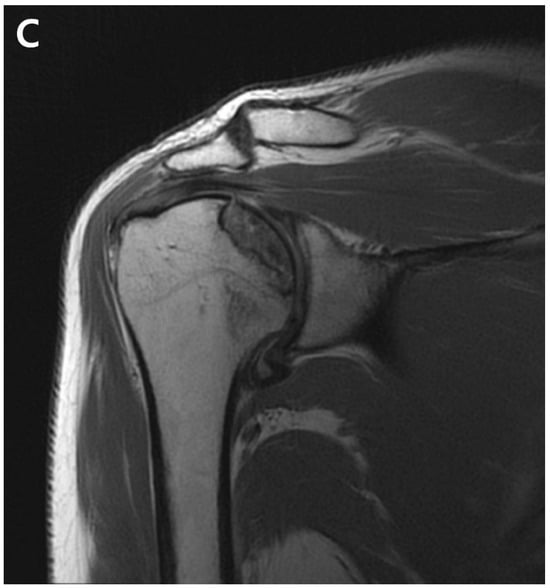

Figure 4.

(A). Postoperative plain radiograph obtained 21 months post-ACR. (B). Oblique coronal T1 fat-suppressed MRI. (C). Oblique coronal T2 fat-suppressed MRI shows osteolytic changes in the superomedial humeral head. MRI shows cystic changes in the epiphyseal area, but articular congruity remains preserved.